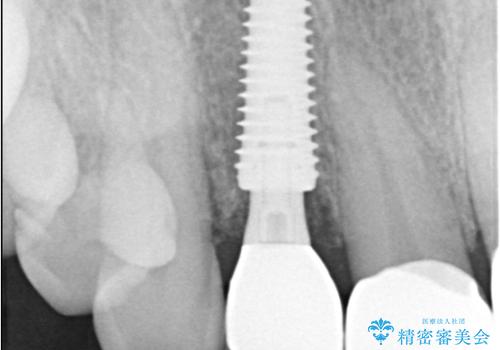

インプラント治療は、低侵襲で短期間に行える「抜歯即時インプラント治療」を選択しました。

この方法は、抜歯したその日にインプラントを埋入し、手術が1回で済むのが大きな特徴です。

治療期間も短く、抜歯からわずか3か月でオールセラミッククラウンを装着することができます。

また、オペ当日には仮歯まで装着するため、見た目を気にせず普段通りの生活を送ることができます。